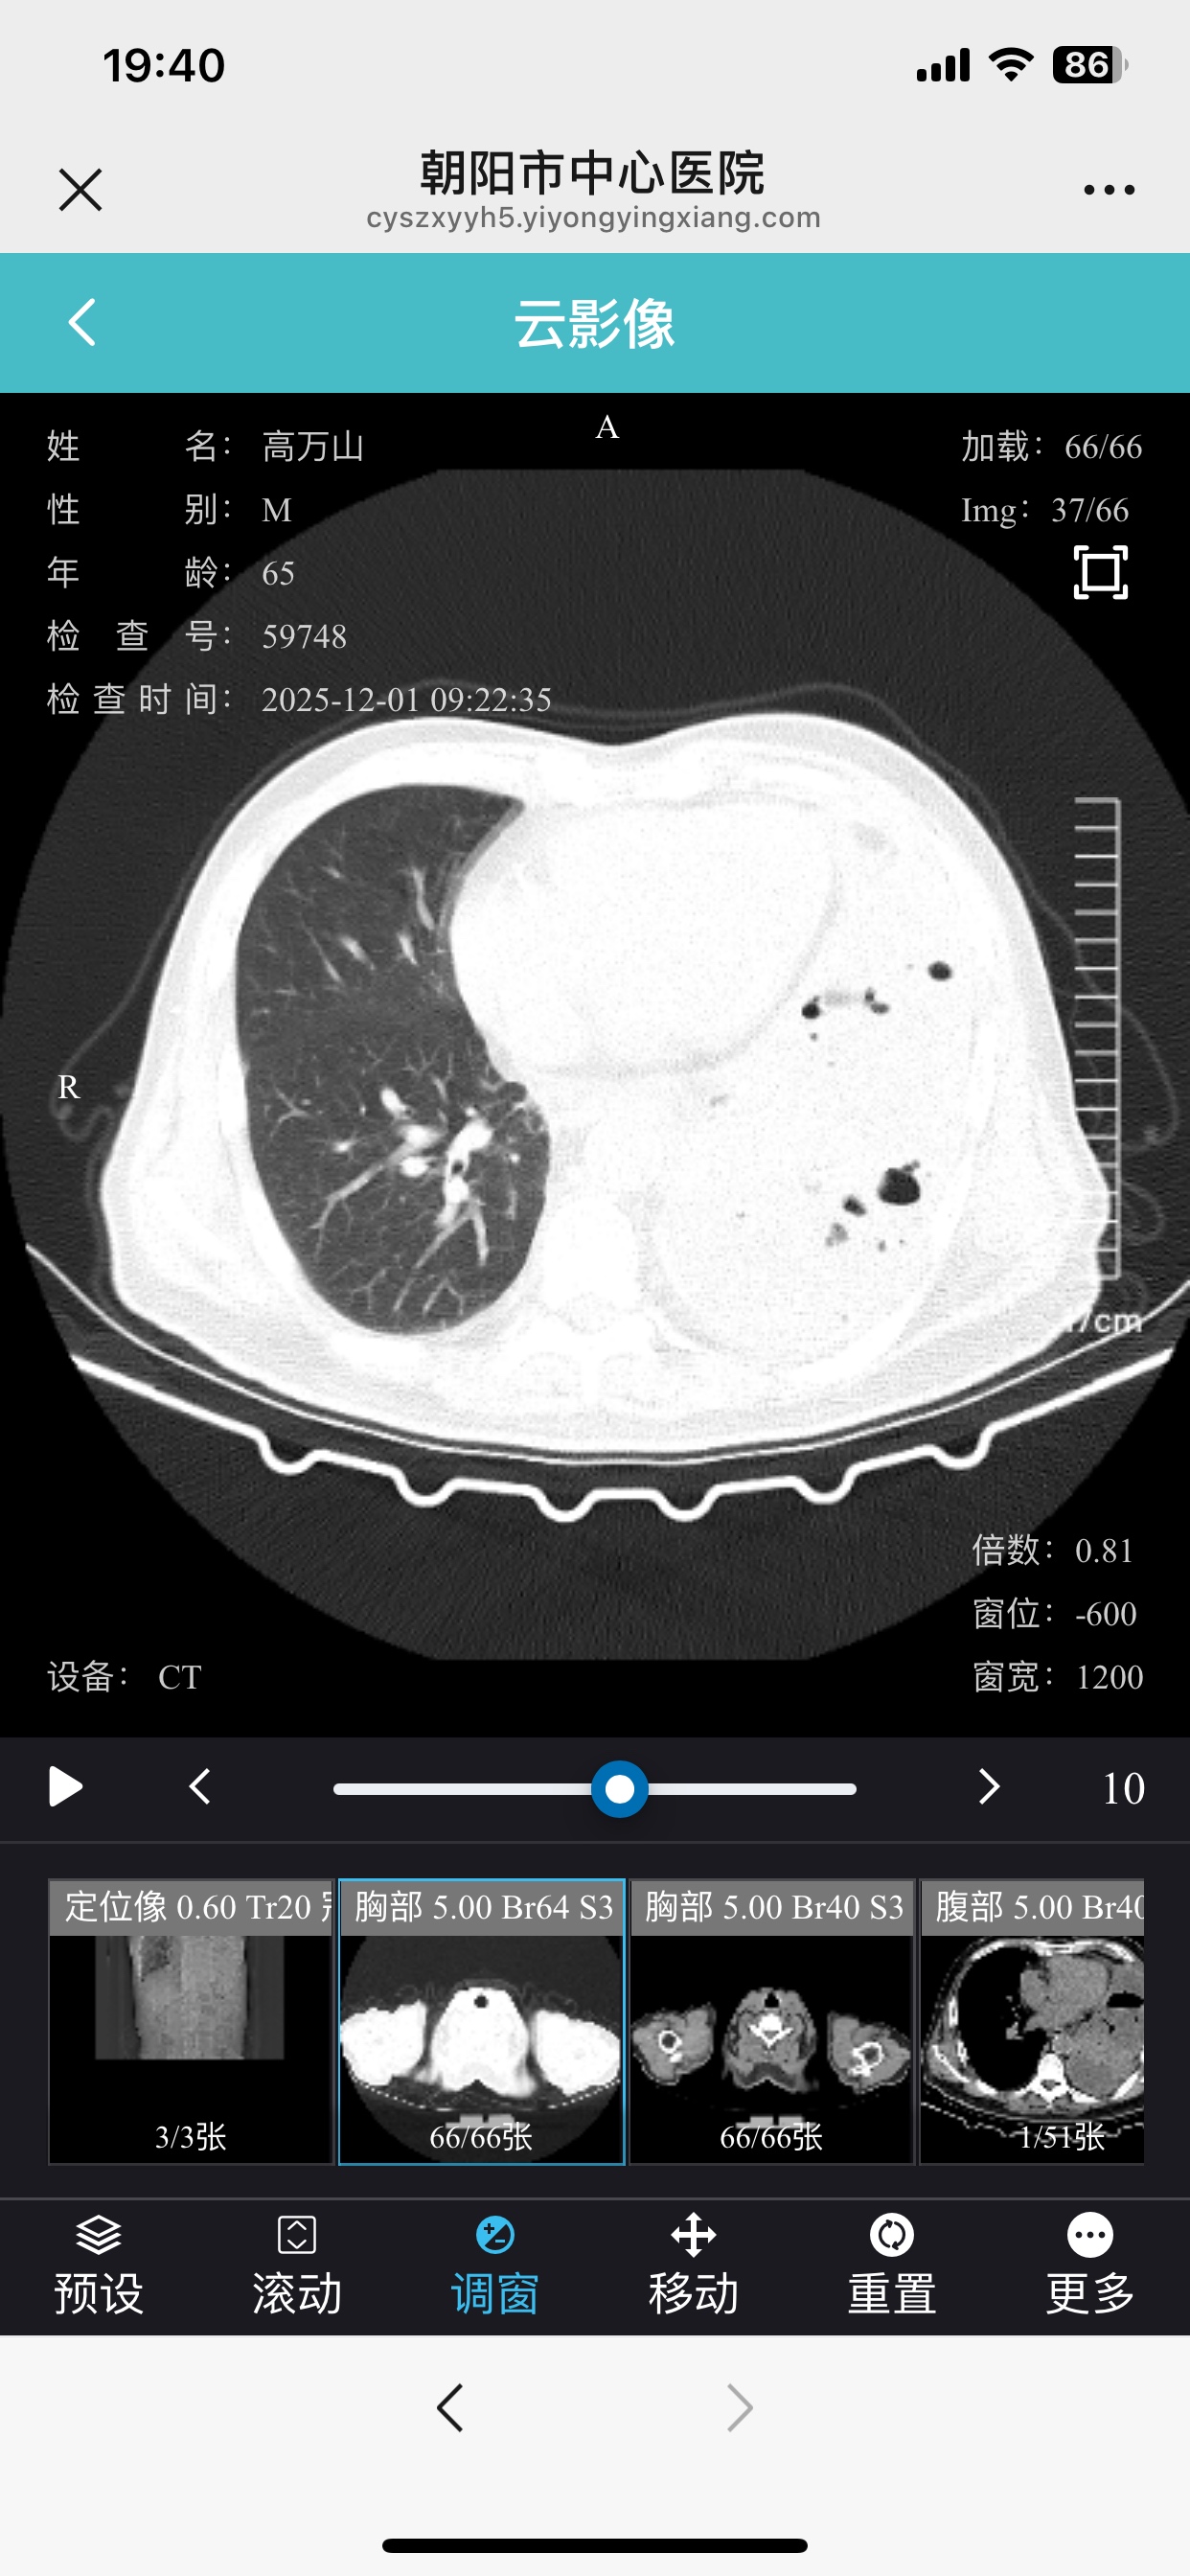

服用吉非替尼21天后复查 癌胚抗原从197升到376 是不是吉非替尼无效啊

登录/注册后可看大图

体感也不太好 拍了ct胸水还是涨起来了

影像为准,如果确实效果不好,换三代再试试

治疗过程尽量详细点,不明确靶点,没有影像复查对比,没办法说效果,还有一个问题,吉非替尼无效,二三代有效率并不高的

拍Ct 肿瘤有变化吗

刚开始吃如果有效肿瘤会缩小